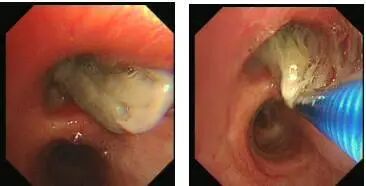

支气管镜下可见右上叶支气管开口可见大量灰黄色脓性分泌物附着管壁,向右上管腔生长,完全阻塞管口,支气管不能进入,坏死物质韧,拉扯不断。

我们取出了很少的分泌物和组织,立刻送检实验室,看到镜下有一些分隔形成的偏细长型的分枝菌丝的表现,这就是真菌感染。在培养下,我们考虑为真菌,主要是毛霉感染。经过标准的两性霉素B治疗,慢慢得到有效吸收。